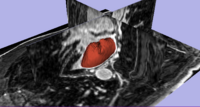

Liver Fibrosis Staging by MRI AnalysisIn this project, we provide tools for robust liver fibrosis staging, based on MRI image analysis. The current practice of fibrosis assessment, which is based on painful liver biopsy, might be dangerous. Moreover, the decision of the pathologist based on a biopsy is subjective, and depends on the sample, because the fibrosis level varies along the liver. No objective standard has been developed yet for histological fibrosis assessment. Magnetic resonance volume data has much lower resolution than histological image data, but it includes the entire liver volume. Also, MRI is non-invasive and not painful, thus it is preferred as a diagnostic tool. Previously it has been hypothesized that the average brightness of Apparent Diffusion Coefficient (ADC) in diffusion MRI correlates with the fibrosis stage. More... | |